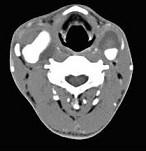

问题 男性,55岁,双侧颈部无痛性包块渐进性增大半年,行CT检查如图所示,请选择最佳答案 ( )

选项 A、双侧颈部肿大淋巴结 B、双侧血管瘤 C、双侧颈静脉瘤 D、双侧颈动脉夹层 E、双侧颈动脉瘤

答案 E